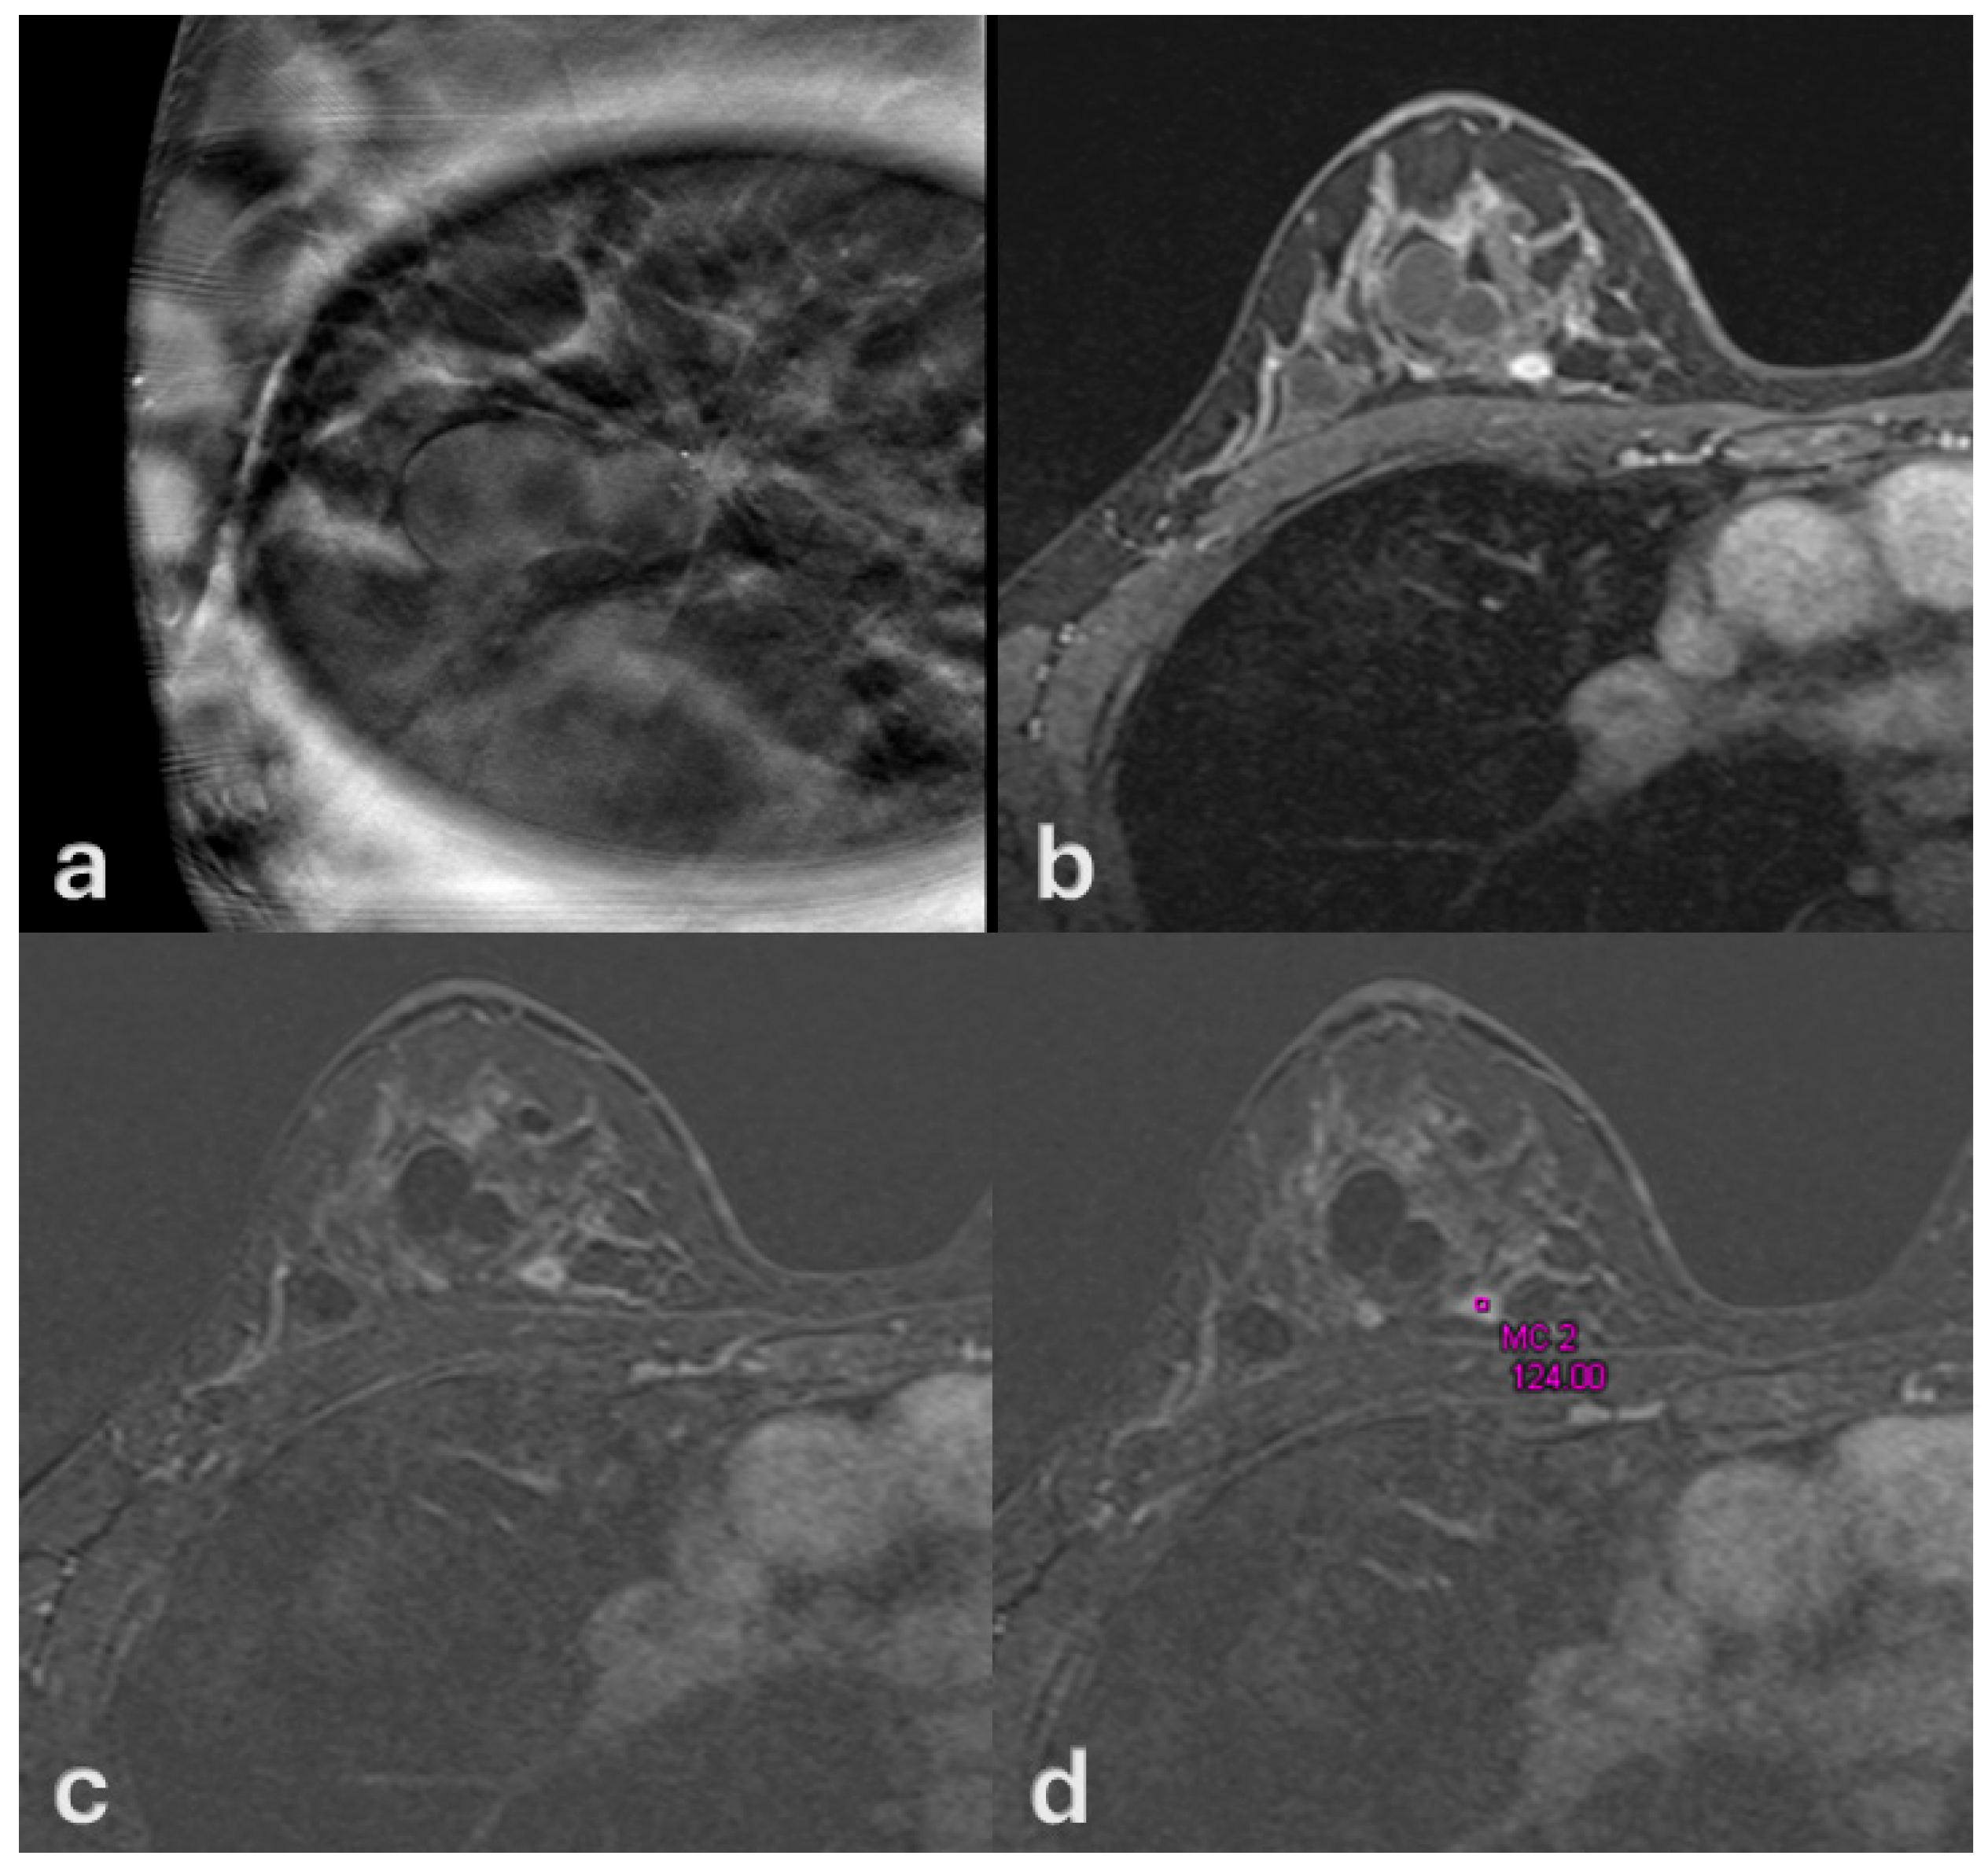

3. Results